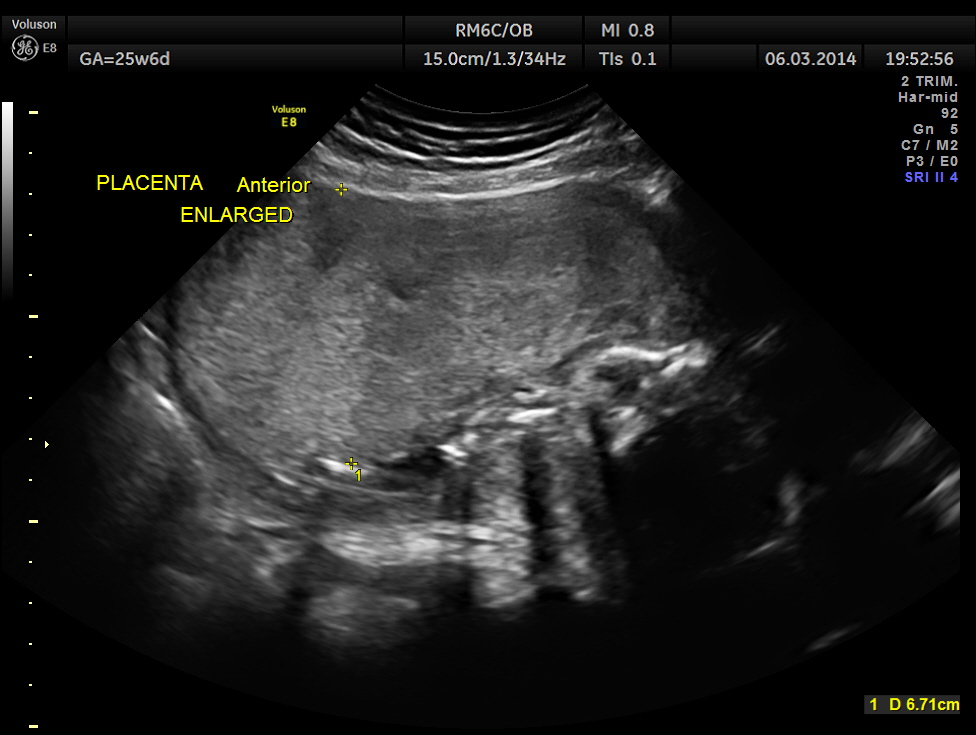

The following report is of the same patient after 5 weeks 3 days.

The GA was around 25 weeks , but the AUA was around 19 to 20 weeks. All parameters – BPD, HC, AC, FL are < 2.3 %tile and all other long bones are < 5.0 %tile.

Prominent placentomegaly seen .

Please look at the placenta again . The infarcts are made out clearly.